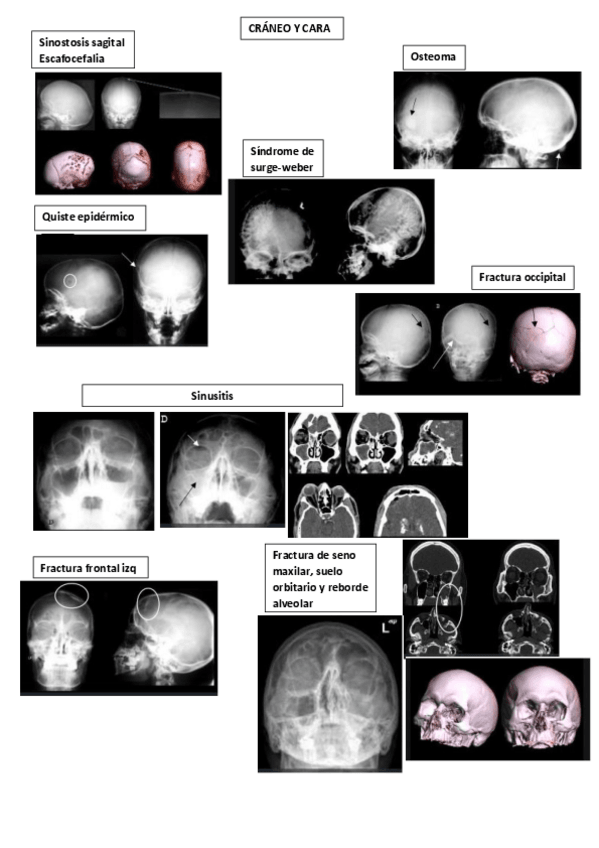

PRACTICA-RADIO-CRANEO.pdf

PracticaCraneo-y-Cara.pdf